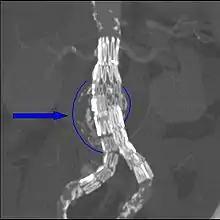

Biomechanical AAA rupture risk prediction

An aneurysm ruptures if the mechanical stress (tension per area) exceeds the local wall strength; consequently, peak wall stress (PWS),[30] mean wall stress (MWS),[31] and peak wall rupture risk (PWRR)[32] have been found to be more reliable parameters than diameter to assess AAA rupture risk. Medical software allows computing these rupture risk indices from standard clinical CT data and provides a patient-specific AAA rupture risk diagnosis.[33][34][35] This type of biomechanical approach has been shown to accurately predict the location of AAA rupture.[34][35][36]